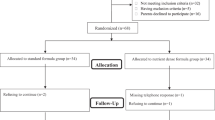

A total of 141 infants who were born with CDH and received treatment for the disease at the five participating institutions were included. Of them, 109 (77%) survived to discharge. Patients with chromosome abnormalities (n = 3), severe cardiac anomaly (n = 5), and very low birth weights (n = 3) were excluded. The remaining 98 patients were included in the present study.

Change in the body weight Z-score is shown in Fig. 1a. The average WGV changed from negative (< 0) to positive (≥ 0) at 2 months of age (WGV between 0 and 1 month, − 1.53/month; WGV between 1 and 2 months, − 0.20/month; WGV between 2 and 3 months, + 0.34/month; WGV between 3 months and 1.5 years, + 1.32/month; WGV between 1.5 and 3 years, + 0.03/month). Figure 1b shows the changes in the body weight Z-score in the dichotomized cohort of severe and non-severe cases. In the severe cases, the bottom of the Z-score was at least after 3 months of age, whereas the bottom of the Z-score in non-severe cases was after 2 months of age.